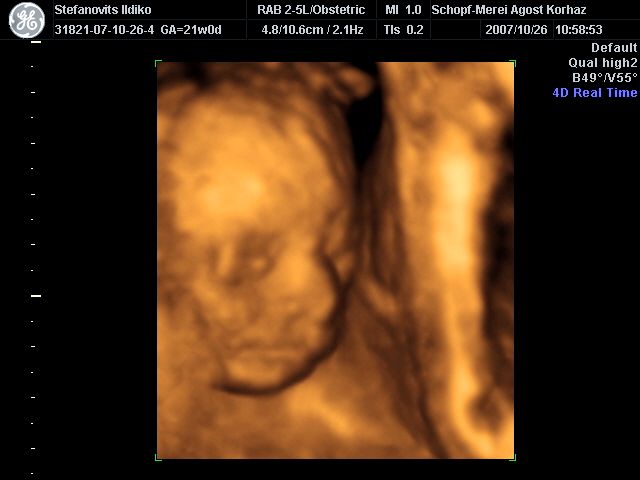

4D Ultrahang - 21+1 (07/10/26, Bp.)

4D - 14